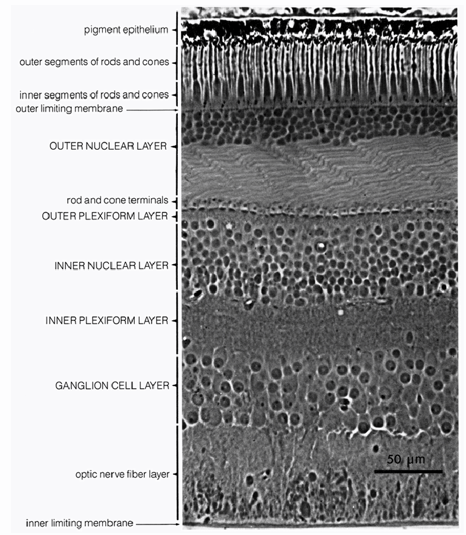

Immerhin enthält die Netzhaut der Augen lichtempfindliche Zellen, die man mit den Pixeln eines Sensors vergleichen könnte. Diese Sinneszellen liegen übrigens recht tief in der Netzhaut, so dass das Licht erst mehrere Schichten anderer Zellen passieren muss, bevor es registriert werden kann. Rund 3/4 des Lichts geht dabei verloren. Wäre die Netzhaut ein Sensor, dann wäre er vom FSI-Typ – ein Sensor mit klassischem Aufbau, bei dem das Licht erst die Schichten der Verdrahtung passieren muss, bevor es auf die Fotodiode eines Pixels trifft. Bei den immer öfter eingesetzten BSI-Sensoren mit umgedrehtem Aufbau liegen die lichtempfindlichen Fotodioden dagegen oben, aber die Evolution hat diesen Schritt noch nicht vollzogen.

Pro Auge gibt es rund 7 Millionen der farbempfindlichen Zapfen, so dass man von 7 MP ausgehen könnten. Dazu kommen aber 125 Millionen nur helligkeitsempfindlicher Stäbchen, womit wir auf 132 MP kämen. Diese Sinneszellen sind jedoch nicht, wie bei einem Sensor, in einem festen Raster angeordnet und auch nicht gleichmäßig verteilt. In einem zentralen Bereich ist die Dichte sehr viel größer als in der Peripherie unseres Gesichtsfelds, in der wir auch keine Farben mehr unterscheiden können. Das Gesichtsfeld, in dem wir wirklich scharf sehen können, umfasst nur etwa 2 Grad, und darin hat das Auge eine Winkelauflösung von rund 0,6 Bogenminuten für ein Linienpaar. Das entspräche dann nur noch einer Handvoll Megapixel. Allerdings wandert unser Blick in einem größeren Gesichtsfeld ständig hin und her, und wenn wir dieses größere Gesichtsfeld mit etwa 120 Grad Breite als Ausgangspunkt der Berechnung nehmen, kommt man auf 576 MP. Auf der anderen Seite gibt es im Sehnerv, der die Netzhaut mit dem visuellen Cortex des Gehirns verbindet, nur eine Million Nervenbahnen – sind es also doch eher nur 1 MP?